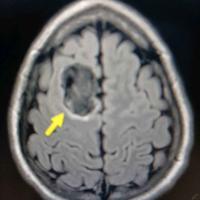

15岁少年在轻度创伤性脑损伤后接受了脑部

15岁少年在轻度创伤性脑损伤后接受了脑部核磁共振,考虑表皮样囊肿,一般手术切除,无症状者勿需治疗。...